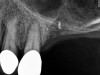

The implant is then delivered and should be well stabilized in the bone. If there is any mobility of the implant, it can either be placed a little deeper (if there is enough native bone) or the implant can be removed and the procedure aborted, in which case it would be a two-stage procedure. This should rarely occur with the tapered designed implant, even with only 2 mm of native bone. Using a bone-level platform-shifting implant (or a tissue-level designed implant) is critical, as the hard and soft tissue will establish a biologic width. If an external hex type of implant is used and the shoulder is placed at the bone level, an expected bone loss of 1.5 mm to 2 mm will occur.24 Figure 10 shows proper bone-level implant depth placement with a platform-shifting design. In this case, a 3-mm healing abutment was placed at the time of surgery to avoid a secondary uncovering surgery, but an implant-level healing abutment could have been placed instead. As can be seen, there was only about 2 mm to 3 mm of native bone height. The membrane was raised about 8 mm to 9 mm. Comparing the radiograph on the day of surgery (Figure 10) to the 6-month postoperative radiograph (Figure 11) shows no loss of native bone, as well as the positive change in appearance of the grafted bone. The 3.5-month CBCT scan (Figure 12) shows good healing of the bone with no coronal bone loss. With minimal native bone present, as in this case, the use of a non-platform-shifting or non-tissue-level implant design could be problematic. After 1.5 mm to 2 mm of crestal bone loss, an external hex designed implant could develop instability with possible implant failure. If a non-tapered implant is used and bone loss occurs during healing, migration of the implant into the sinus could potentially occur. The surgeon can use either a healing abutment or implant-level closure screw over the implant shoulder. With patients who tend to use their tongues to explore or play with the area, or if the area is under a removable partial denture, a closure screw is recommended.

This patient was a 73-year-old man with only about 3.5 mm of native bone in the No. 3 site (Figure 20). The composite graft used here was a 50:50 mixture of DFDBA and deproteinized bovine bone mineral (Osteohealth, www.osteohealth.com) with approximately 40% calcium sulfate added. The implant was the same type and length as in Case 1 above. Figure 21 shows the area on the day of placement. In the CBCT scan on the day of placement (Figure 22), the native bone and bone graft were clearly discernable. However, the postoperative radiograph taken at 6.5 months (Figure 23) showed no marginal bone loss and a significantly denser appearance than when the graft was place. The membrane was raised about 7 mm to 8 mm. The final radiograph was taken after extraction of tooth No. 2 and after extraction of tooth No. 4 and immediate implant placement.